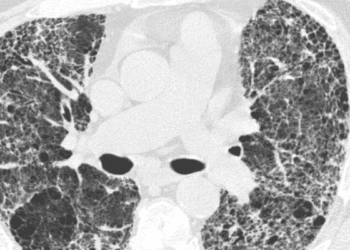

Image: PD/ Fibrotic lung 1. Ambrisentan is ineffective in delaying disease progression in idiopathic pulmonary fibrosis (IPF). 2. Compared to placebo, ...